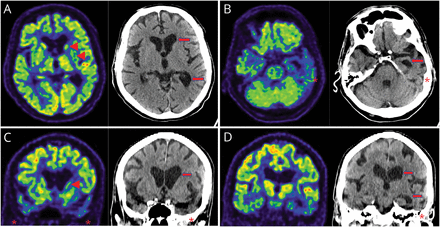

血清学的检测获得的代谢紊乱、维生素缺乏、感染、自身免疫,和多种的原因是noncontributory。大脑的核磁共振显示明显不对称左左前颞叶和海马和双边尾状萎缩。也有轻度到中度广义幕上的萎缩没有白质异常信号(图1)。

前颞叶所示冠状平面在t1 (A)和t2加权磁共振序列(B)。有不对称的左内侧颞叶萎缩与相应的侧脑室颞角增大。也有左额叶的体积损失的重要性在额叶和颞叶沟的空间。

神经FDG PET / CT显示不对称(左比右)颞叶萎缩与葡萄糖代谢减退。有降低新陈代谢的头部的左侧尾状核(图2)。C9ORF72基因测试显示没有病理重复扩张等位基因;然而,测试的杭丁顿蛋白(计画)基因显示扩大39 CAG重复1等位基因和18重复。

成对FDG PET / CT transaxial(上面一行)和冠状(行)图像在基底神经节的水平(A, C)伪劣颞叶(B, D)。在A和C,有明显降低葡萄糖代谢的头左尾状核和壳核(箭头)和非对称放大额叶和左枕角(箭头)和代谢减退前颞叶(左>右,明星)。在B和D,标志着颞叶萎缩(左>右,明星)扩大左颞额角(箭头)和相应的显著减少代谢在颞叶(左>右,明星)。